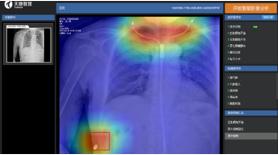

为此,天地智慧医疗专门开发了——全链AI胸部影像智能分析系统,影像科医生通过全链AI服务可以辅助医生使用云PACS进行影像快速筛查,大幅提升医生诊断效率。全链AI胸部影像智能分析系统包含采集控制AI、影像分析AI、阅片诊断AI、科室管理AI等,辅助医生从拍摄到诊断的影像全流程。

尤其在胸部正位常见疾病AI辅助诊断有着高于同行业的诊断准确率。天医云全链AI,针对体检中常见的十四种胸部肺部疾病(包括肺结节、肺水肿、肺不张、肺实变、气胸、肺炎等)及职业病(肺结核、尘肺矽病等)最高可实现诊断准确率(AUC)92.6%、灵敏度96.2%和特异性85.1%的优异表现,可极大程度有效提升胸部X-射线影像检查效率和诊断质量。

全链AI胸部影像智能分析系统基于基于计算机视觉算法、大数据训练、神经网络的深度学习,将AI融入到放射医学影像全流程中,实现智能检索,海量筛查以及精确诊断,为临床提供更高质量超清影像,并以一致客观的量化标准实现自动化测量、批量数据准确筛查和多类型病灶智能提示功能,有效提升临床诊断质量、效率和收益,强化体检中心在同等规模体检中心的竞争力,减低阅片医生工作负担并优化患者就诊体验。